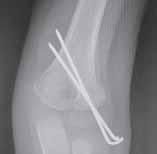

Rycina 17.81.

A, B – Genu recurvatum u pacjenta po złamaniu okolicy proksymalnej części chrząstki nasadowej piszczeli.

Rycina 17.82.

Uszkodzenie tętnicy podkolanowej wskutek złuszczenia nasady bliższej kości piszczelowej (S-H 1). Zagrożenie rozwojem zespołu przedziałów powięziowych jest poważne.